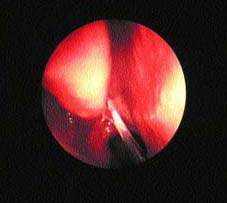

| Рисунок 3. Гной в среднем носовом ходе при остром синусите |

В некоторых случаях имеются местные симптомы, позволяющие заподозрить вовлечение различных синусов. При диагностике наиболее достоверным симптомом является жалоба на гнойные выделения из носа или выявление их при обследовании (рис. 3).